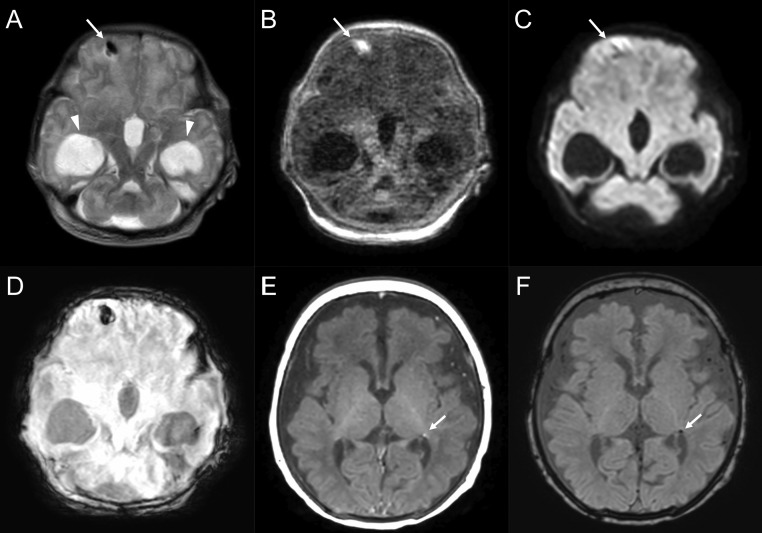

All the nine neonates with neurological abnormalities had abnormal neuroradiological findings. The neuroradiological characteristics of the nine neonates are summarized in Table 2. Of the nine neonates with neuroradiological abnormalities, seven were in the Sym-M-N group. All the neonates with neurological abnormalities developed respiratory failure that needed NICU admission. Of these, four (44.4%) were very preterm and two (22.2%) were preterm. The most common imaging feature was intracranial hemorrhage (germinal matrix hemorrhage, n = 2 [22.2%]; parenchymal hemorrhage, n = 2 [22.2%]; intraventricular hemorrhage, n = 1 [11.1%]), followed by hypoxic brain injury (diffuse white matter and magnetic resonance spectroscopy abnormalities, n = 2 [22.2%] each; FIGURE 1, FIGURE 2, FIGURE 3 ). Patient 5, with a right frontal lobe hematoma, was diagnosed with holoprosencephaly, and patient 6, with hypoxic-ischemic injury (HIE), was born to a mother with placental abruption.

Cases with hypoxic-ischemic encephalopathy. A 31-weeks-and-1-day-old female born to a coronavirus disease 2019 (COVID-19) symptomatic mother. The neonate had minimal reaction to physical examination and a cloverleaf skull deformity (patient 4). Magnetic resonance imaging on the fifth day after birth shows bilateral diffuse white matter abnormalities on a fluid-attenuated inversion recovery image (A, arrows), diffusion-weighted image (B, arrows), and T1-weighted image (C, arrows) with cortical T1 hyperintensity corresponding to cortical laminar necrosis (arrowheads). On the susceptibility-weighted image, a microbleed is observed in the left periventricular white matter (D, arrow). A 35-weeks-and-6-day-old female born to a COVID-19 asymptomatic mother who had a placental abruption (patient 6). The neonate had decreased muscle tone and activity. Diffuse signal abnormality in bilateral deep nuclei and white matter is observed on a T2-weighted image (E), T1-weighted image (F), and diffusion-weighted image (G). Intraventricular hemorrhage is observed in the dorsal horn of the right lateral ventricle (H; arrow; susceptibility-weighted image).

FIGURE 3.

Cases with intraparenchymal hemorrhage. A 35-weeks-and-1-day-old male born to a coronavirus disease 2019 (COVID-19) symptomatic mother (patient 5). The neonate had delayed bilateral Babinski reflexes, neurobehavioral instability, and hypotonia. Magnetic resonance imaging (MRI) on the first day after birth shows bilateral ventriculomegaly (arrowheads), semilobar holoprosencephaly, and intraparenchymal hemorrhage in the right frontal lobe (short arrows; A: T2-weighted image, B: T1-weighted image, C: diffusion-weighted image, D: susceptibility-weighted imaging). A 40-weeks-and-5-day-old male born to a COVID-19 symptomatic mother (patient 8). The neonate had pinpoint pupils and decreased muscle tone, with concern for hypoxemic-ischemic encephalopathy in the setting of meconium aspiration syndrome. MRI on the twelfth day after birth shows a tiny focus of prior ischemic change in the left periventricular white matter (arrows; E: T1-weighted image, F: susceptibility-weighted image).